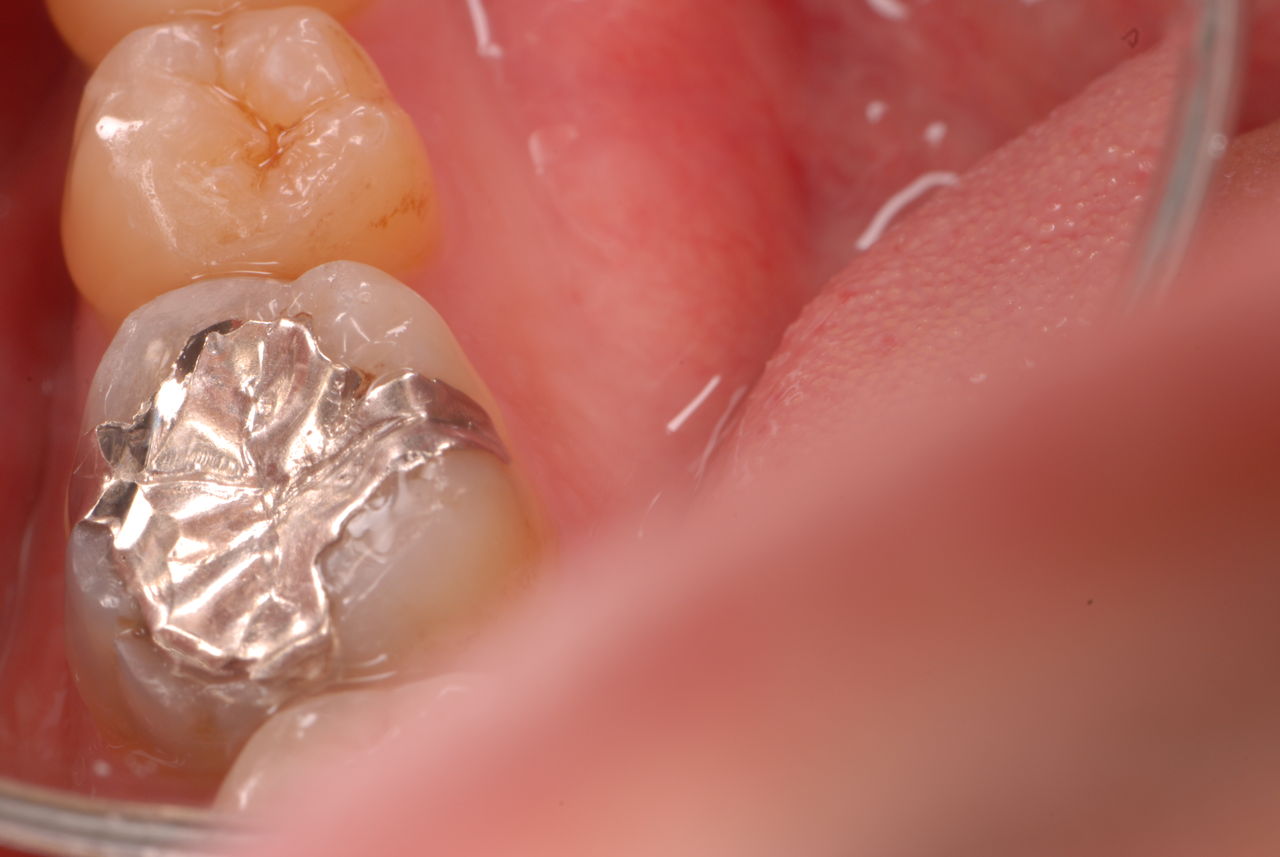

30代の男性の方です。

入れ歯を入れていました。歯科医院で歯を抜けず仕方なく入れ歯にしたとか。何とかならないものだったのか悔やまれました。

抜いた歯はありません。

一応差し歯にしましたが、歯茎の状態はよくはありません。

とりあえず希望を入れて差し歯にしたような感じです。